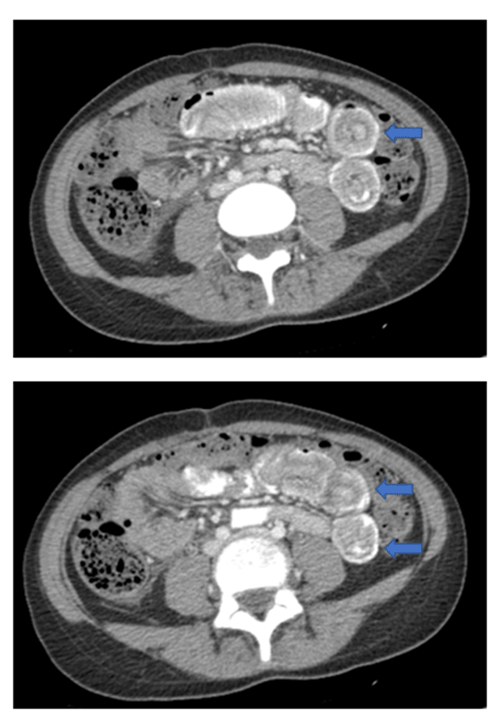

At the time of her second evaluation, she was febrile to 104°F with hypotension and tachycardia. She complained of abdominal pain and poor appetite. The patient was pancytopenic with a hemoglobin of 7.1 g/dL, white blood cell count of 0.2 thou/cmm, and platelets of 92 thou/cmm. Her lactate was elevated to 6.2 mmol/L. CT imaging of the abdomen was suggestive of three distinct areas of intussusception within the small intestine, and no discrete lead points were seen (Figure 2).

Figure 2. CT Scan of Abdomen with IV and Oral Contrast, Suggestive of Three Distinct Areas of Intussusception within Small Intestine (blue arrows). Published with Permission

CT Scan of Abdomen with IV and Oral Contrast, Suggestive of Three Distinct Areas of Intussusception within Small Intestine (blue arrows).

No discrete lead points were identified. No obstruction or bowel thickening was present. There was edema along the right psoas muscle and no findings of appendicitis or diverticulitis.